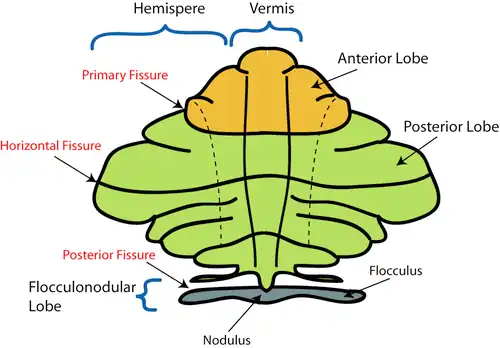

The cerebellar vermis (from Latin vermis, "worm") is located in the medial, cortico-nuclear zone of the cerebellum, which is in the posterior fossa of the cranium. The primary fissure in the vermis curves ventrolaterally to the superior surface of the cerebellum, dividing it into anterior and posterior lobes. Functionally, the vermis is associated with bodily posture and locomotion. The vermis is included within the spinocerebellum and receives somatic sensory input from the head and proximal body parts via ascending spinal pathways.[1]

Structure

The vermis is the unpaired, median portion of the cerebellum that connects the two hemispheres.[9] Both the vermis and the hemispheres are composed of lobules formed by groups of folia. There are nine lobules of the vermis: lingula, central lobule, culmen, clivus, folium of the vermis, tuber, pyramid, uvula and nodule.[9] These lobules are often difficult to observe during human anatomy classes and may vary in size, shape and number of folia. It has been shown that folia of the cerebellum exhibit frequent variations in form, number and arrangement between individuals.[9]

Lobe anatomy

The lingula is the first lobule of the upper portion of the vermis on the superoinferior axis and pertains to the paleocerebellum together with the central lobule, culmen, pyramid and uvula. It is separated from the central lobule by the pre-central fissure. The central lobule is the second lobule of the upper portion of the vermis on the superoinferior axis. The culmen is the third and largest lobule of the upper portion of the vermis on the superoinferior axis. It is separated from the declive by the primary fissure and is related with the anterior quadrangular lobule of the hemisphere. The pyramid is the seventh lobule of the vermis on the superoinferior axis. It is separated from the tuber and uvula by the pre-pyramidal and secondary fissures, respectively.[9] This lobule is related with the biventral lobule of the hemisphere. The uvula is the second largest lobule, following the culmen. It pertains to the paleocerebellum and is separated from the nodule by the posterolateral fissure.[9]